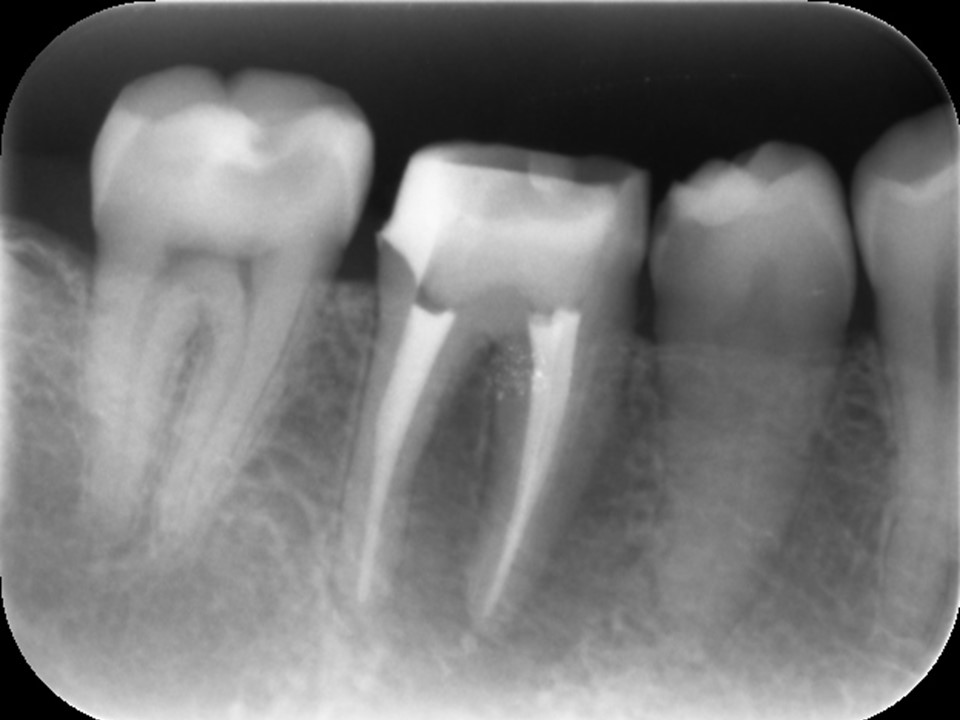

| 治療前レントゲン | 治療前CT |

|---|---|

| 治療前レントゲン |

|---|

| 治療前CT |

根管充填後レントゲンおよびCT画像です。

症状が消失したため、ガッタパーチャとバイオセラミックシーラーにて根管充填を行いました。炎症が強かったため、歯槽骨の吸収の範囲が術前よりも広がっています(矢印)。